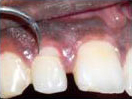

Dead discolored tooth

with a growth in bone

The Smile after placing

the Temporary Crown.